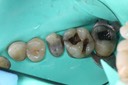

Kyle Chock #15 pre-op

Kyle Chock #15 caries removal

Kyle Chock #15 prep